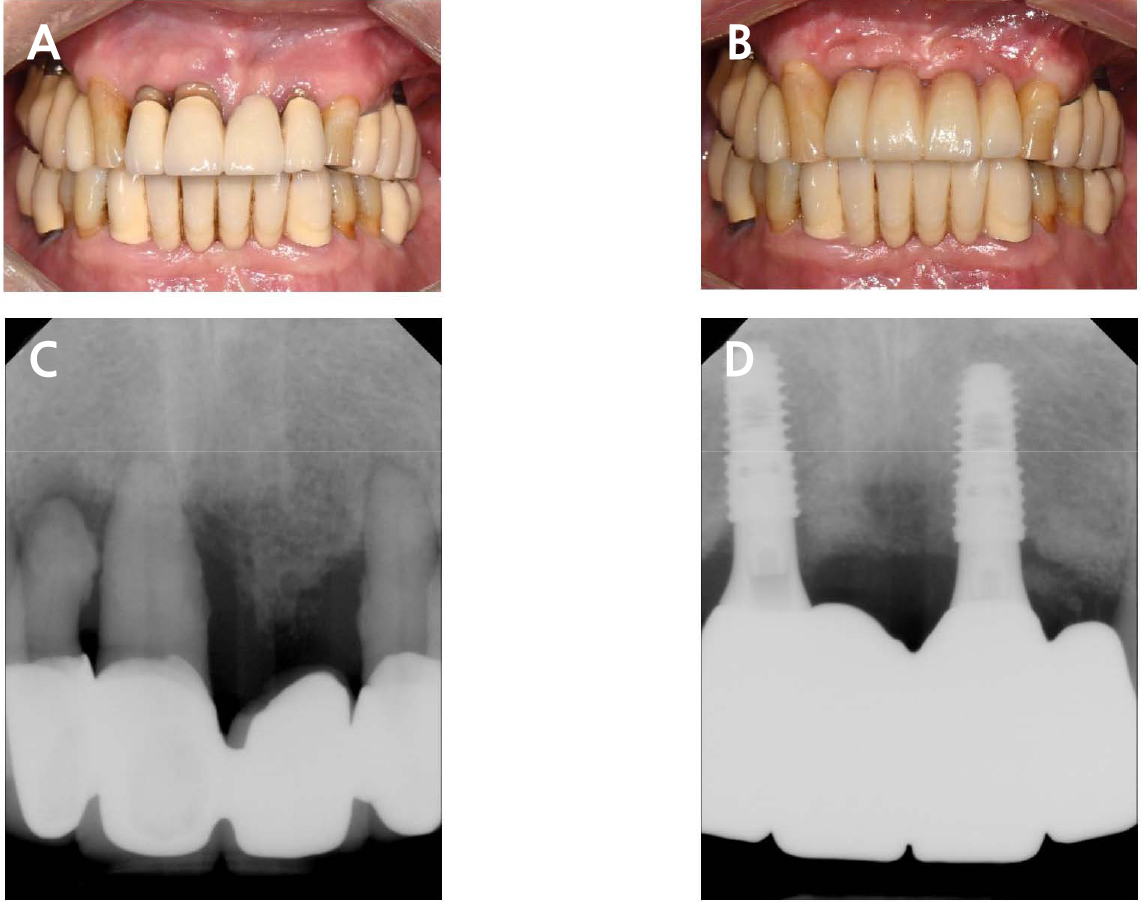

During the intraoral clinical examination, healthy peri-implant mucosa was observed, and no signs of inflammation, such as suppuration, edema, or rash, were observed. The radiograph obtained after connecting the final prosthesis revealed that the implant was located approximately 1–2 mm from the alveolar bone, and no bone loss was observed (Fig. 3). The patient was satisfied with the implant restoration.

Fig. 3.

Pre- and postoperative buccal views and periapical radiographs of the anterior maxillary area. (A) Preoperative buccal view of the anterior maxillary area, (B) Postoperative buccal view of the anterior maxillary area, (C) Preoperative periapical radiographs of the anterior maxillary area, (D) Postoperative periapical radiographs of the anterior maxillary area.